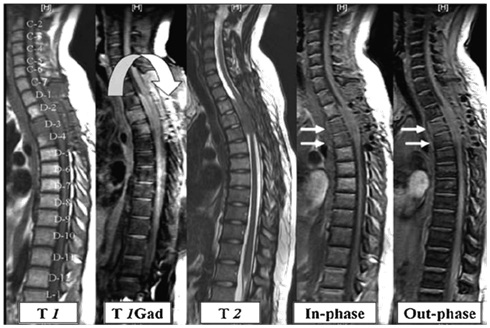

Establishing the accurate diagnosis is of great importance in determining treatment, surgical intervention, and prognosis. T1- and T2-weighted sequences without or with fat saturation show similar signal intensities for both benign osteoporotic and neoplastic fractures [Figure 1 & 2]. Thus, the morphology of bone marrow replacement has been evaluated for prediction of the benign or pathologic cause of a fracture. Paravertebral soft-tissue masses [Figure 2] and infiltration of posterior elements [Figure 2] are the most reliable MRI signs of a malignant fracture.10

Figure 2 Patient with bronchogenic carcinoma showing multiple neoplastic infiltrative lesions in D12, L1, and L2 vertebrae, they reflect bright signal on STIR sequence with bulging posterior border of L2 (white curved arrow). No significant signals drop on out of phase image relative to in-phase images.

Marrow infiltrative processes, such as malignant neoplasms, tend to replace the fatty marrow components completely. Accordingly, researchers have hypothesized that chemical shift MR imaging might be a useful technique for the evaluation of axial bone marrow lesions. Chemical shift MR imaging can demonstrate the relationship between the amount of fat and water that coexist in the same voxel. Osseous elements, however, will also affect this relationship; thus, the degree of signal intensity change may not be proportional to the quantity of hematopoietic marrow alone. Hemangiomas for example are slowly growing, benign neoplasms that are commonly found in the vertebral bodies. Histopathologically, they consist of thin-walled, blood-filled vessels and sinuses that are lined by endothelium, are interspersed among the bone trabeculae, and have a variable amount of fat. Some, such as those with predominant fat content, do not demonstrate a drop in signal intensity because there are few or no nonlipid elements. However atypical hemangiomas [Figure 3], which contain only small or microscopic quantities of fat, may demonstrate the utility of chemical shift MR imaging because they will lose signal intensity on out-of-phase images.15

Ragab et al. 7 established the cut-off value of the signal intensity drop on chemical shift (MRI) to obtain appropriate sensitivity, specificity and cut off value to differentiate osteoporotic from neoplastic wedging of the spine. In their study a total of 40 patients were recruited, 20 with osteoporotic wedging [Figure1] and 20 neoplastic [Figure 2 & 3]. In their study the authors observed a substantial reduction in signal intensity in all lesions in both groups. The proportional changes observed in signal intensity of bone marrow lesions on in-phase compared with out-of-phase images showed significant differences in both groups (P < 0.05). At a cut-off value of 35%, the observed sensitivity of out-of-phase images was 95%, specificity was 100%, positive predictive value was 100% and negative predictive value was 95.2%. In contrast to the study by Ragab et al.7 Zajick et al.15 suggested that a decrease in signal intensity greater than 20% on out-of phase images compared with in-phase images should be used as a cut-off threshold for normality to allow distinction between benign and neoplastic vertebral marrow lesions.